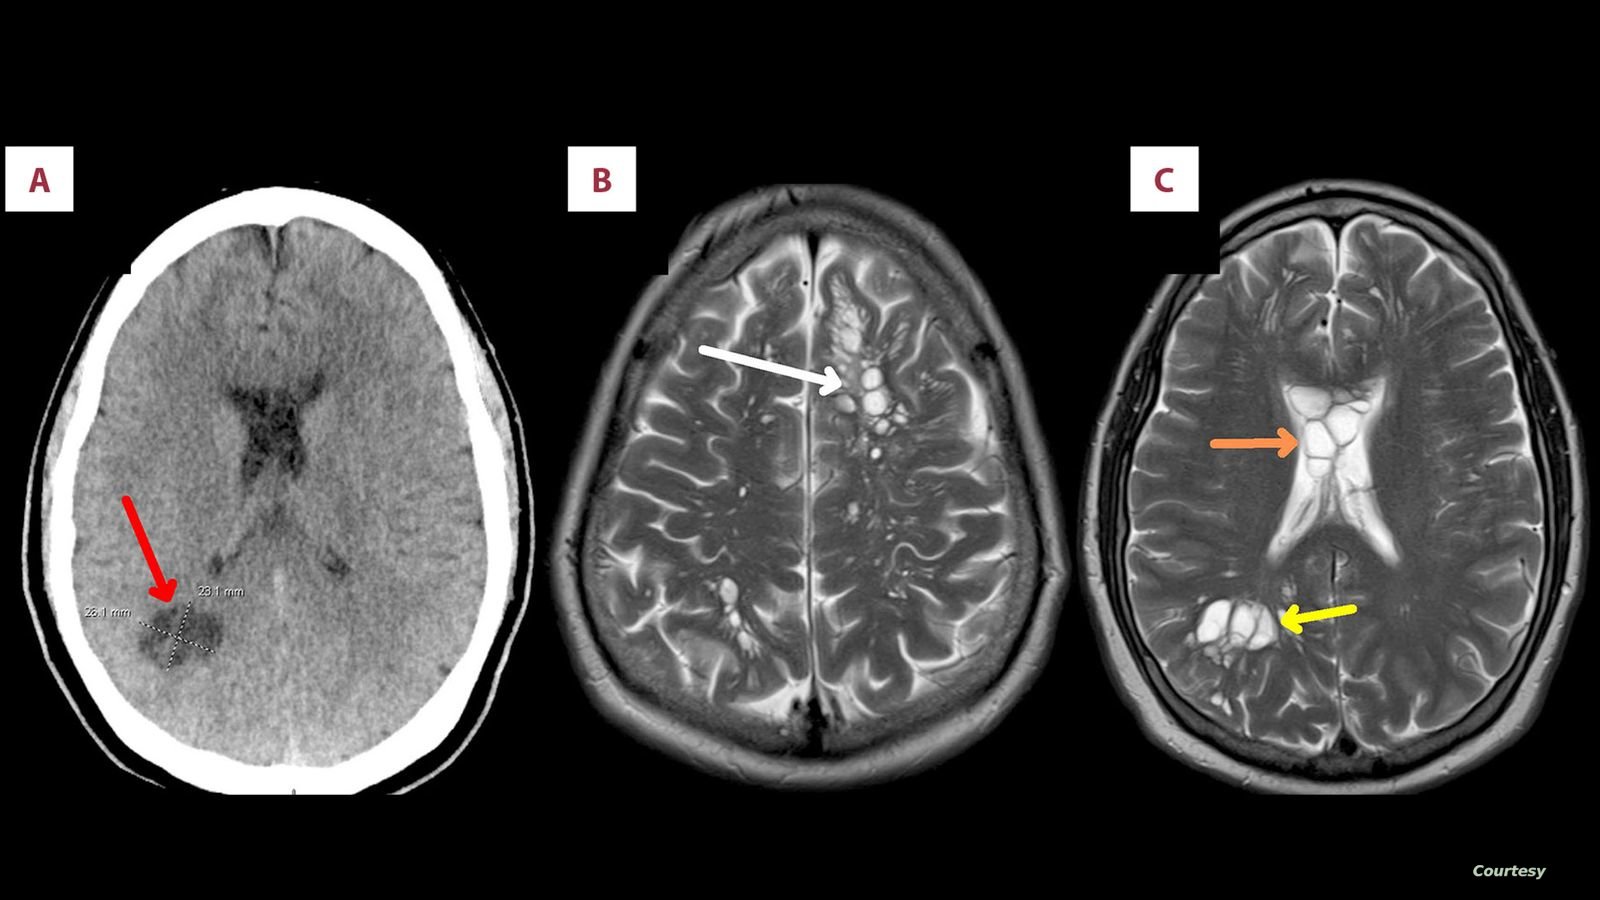

اكتشفت رجل أمريكي في الخمسينات من العمر  وجود بيض الدودة الشريطية في دماغه بعد زيادة آلام الصداع النصفي التي كان يعاني منها.

وأوضح الأطباء أن مرد هذه الحالة كان سببه، تناول الرجل لحم الخنزير المقدد غير المطبوخ جيدًا، وفقا لما ذكرت شبكة “سكاي نيوز” البريطانية.

وكشف تصوير بالأشعة المقطعية أجراه أطباء لدماغ الرجل، عن بيوض الدودة الشريطية، وتم تشخيص المريض بداء الكيسات المذنَّبة العصبي.

وذلك الداء هو نوع خاص من داء الكيسات المذنبة، يحدث بسبب عدوى بالشريطية الوحيدة، وهي شريطية حقيقية (Eucestoda) تُوجد في الخنازير، والتي يمكن أن تصل إلى الأنسجة مثل العضلات والدماغ.